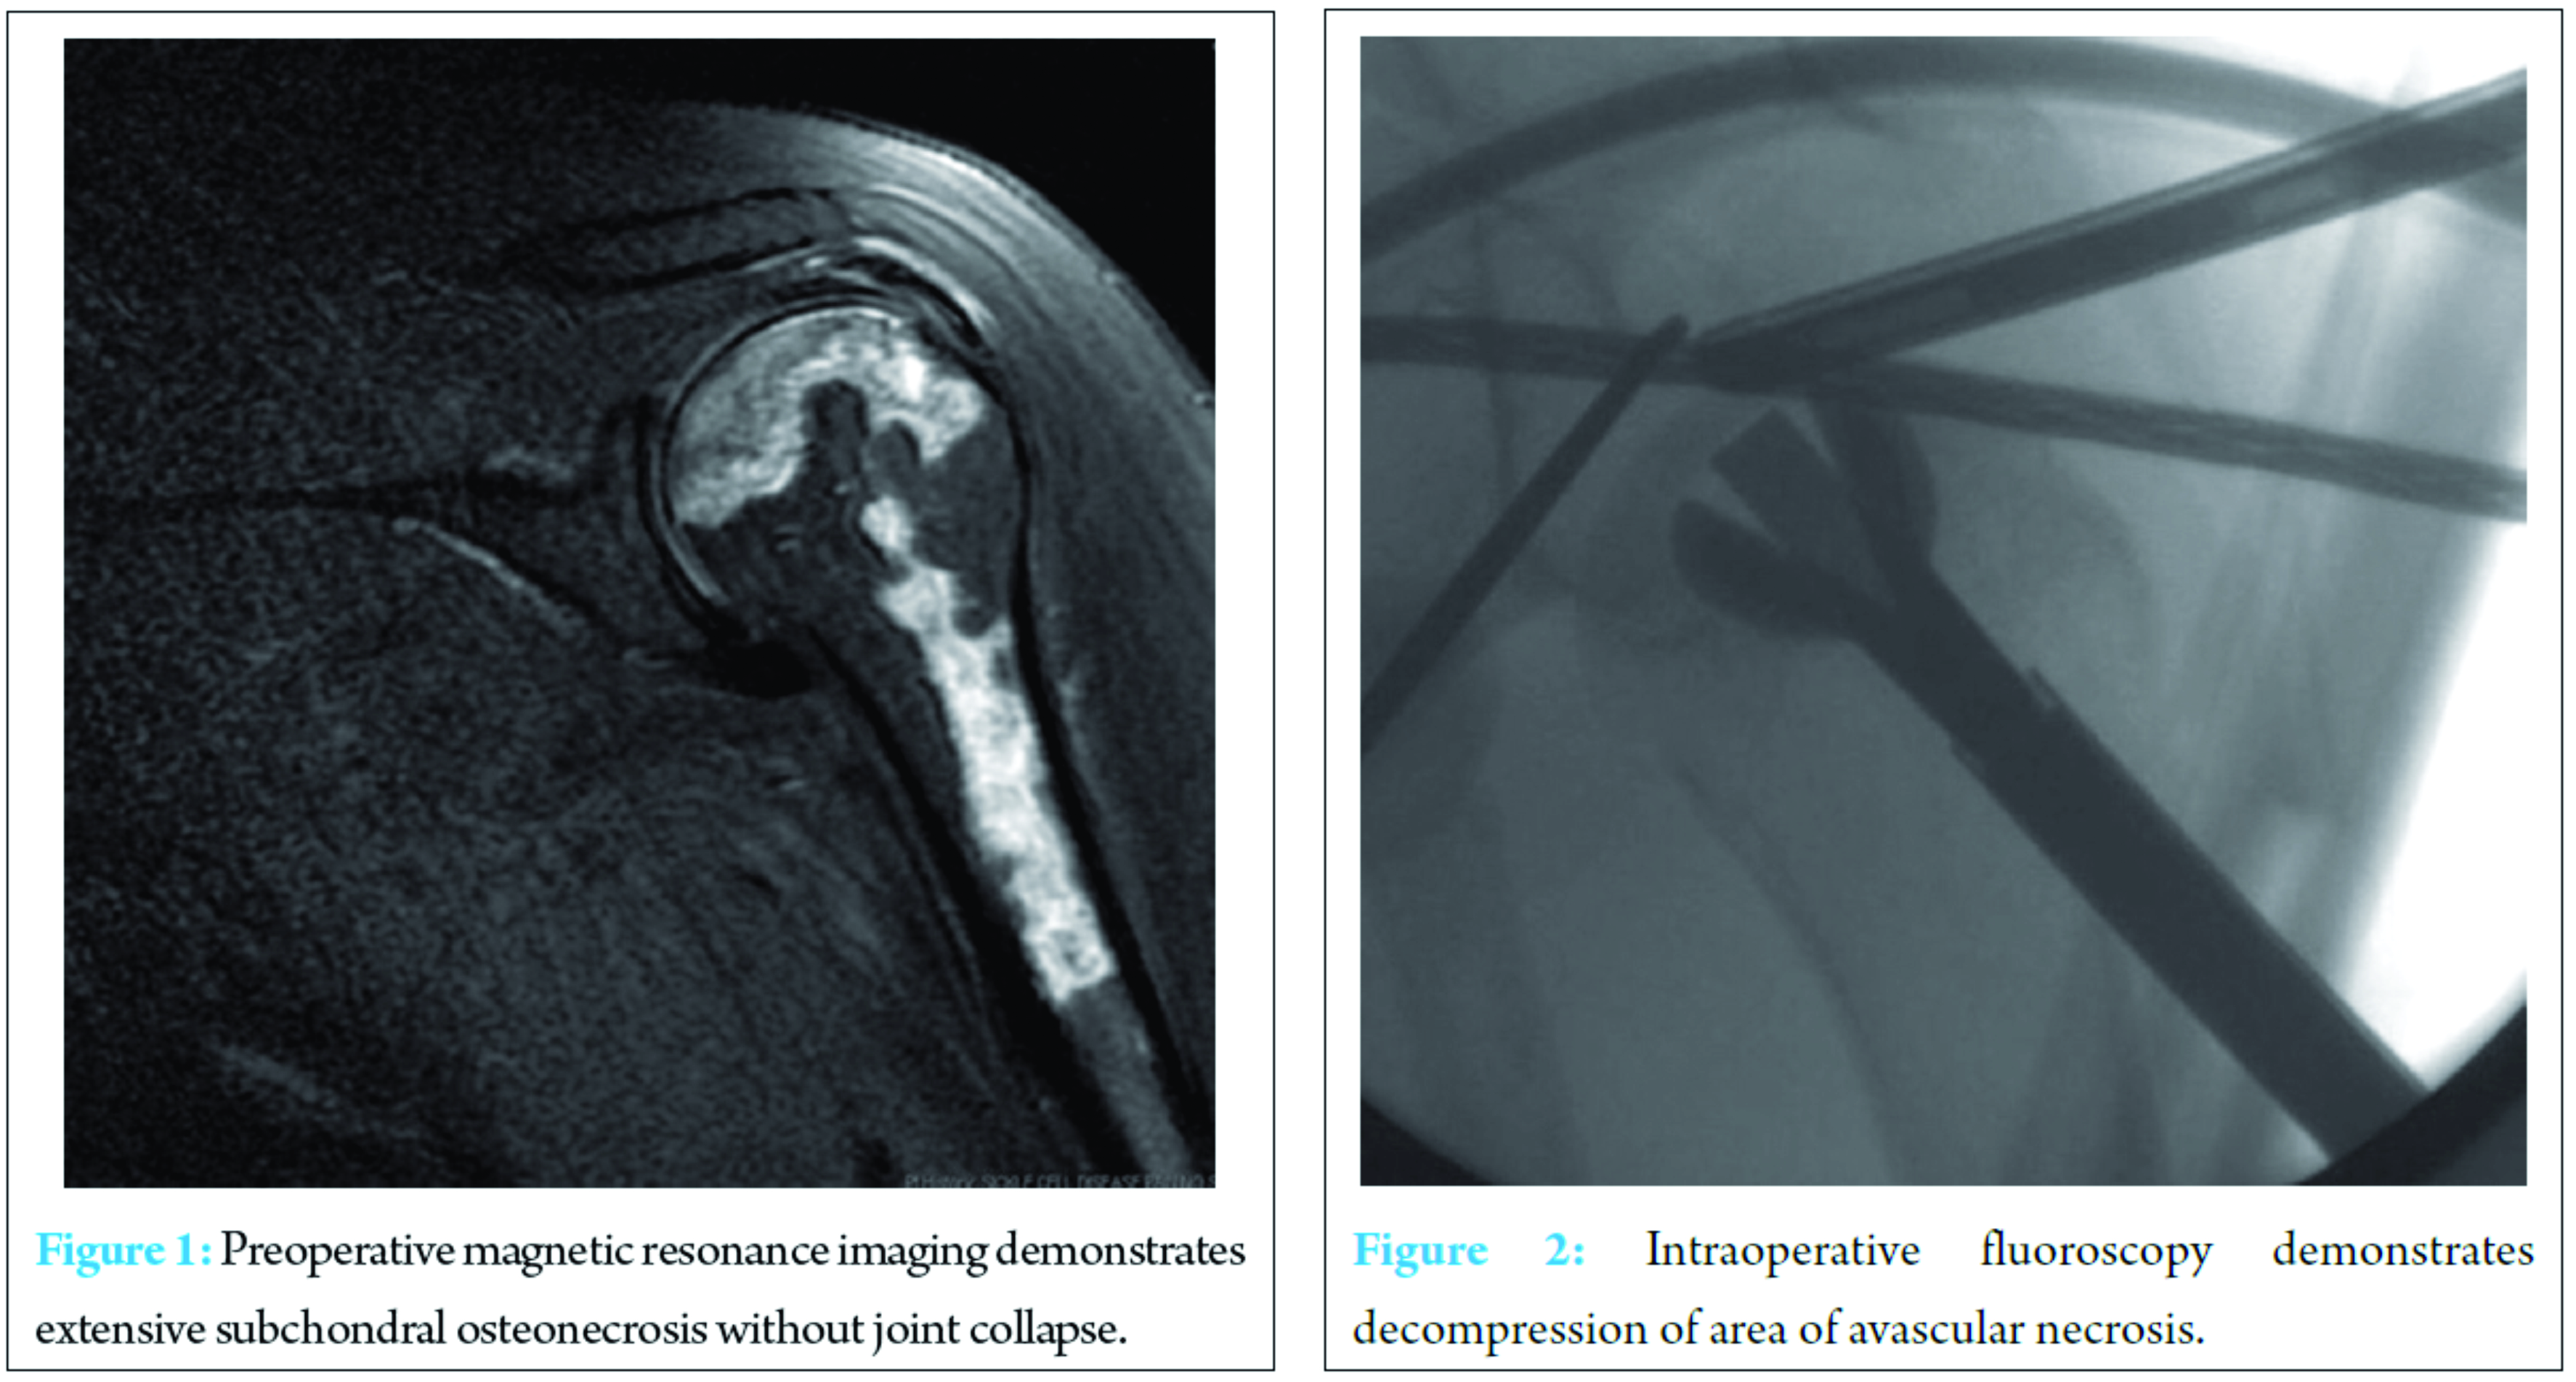

A 51-year-old African-American woman with a history of sickle cell anemia presented for the evaluation of significant bilateral shoulder pain that was interfering with her activities of daily living and requiring narcotic medication for pain control. The pain and disability had been increasing progressively over several years and was recalcitrant to physical therapy. Radiographs and magnetic resonance imaging (MRI) confirmed AVN of her humeral heads without joint collapse (Fig. 1).

Staged surgery was then performed approximately 4-month apart using the identical technique on both shoulders. Our standard perioperative protocol for sickle cell patients was utilized. This consists of admission the evening before surgery to the internal medicine service with acquisition of routine blood work, intravenous hydration, and preoperative blood transfusion as indicated based on hemoglobin level [9]. Surgery was performed in the beach chair position with the c-arm coming in perpendicular to the patient. Diagnostic arthroscopy was performed to evaluate for intra-articular pathology and confirm that there was no significant chondromalacia, which would negate the benefits of the joint preservation procedure. In this case, arthroscopy revealed small partial thickness articular sided supraspinatus tears that were debrided but no visible chondral damage was present. Upon probing, the cartilage was quite soft over the areas of AVN noted on MRI. Under fluoroscopic guidance, a guide wire was directed into the center of the region of AVN, which was done via a small deltoid splitting approach laterally. The arthroscopic probe was placed in the center of the most depressible cartilage region on the head and utilized fluoroscopically to guide pin placement. Once the guide wire was in the center of the defect, an expandable reamer was utilized and the necrotic bone was removed (Fig. 2).  The arthroscope is critical in this stage to allow complete extraction of necrotic subchondral bone while ensuring no penetration of the cartilage. After full decompression was performed, synthetic bone graft (PRO-DENSE, Wright Medical) was injected under fluoroscopy and direct visualization. Given the immediate structural integrity of the graft, maximal removal of necrotic segments was attempted. Care was taken under fluoroscopic guidance not to penetrate the articular surface and no cartilaginous defects were encountered. For both procedures, the standard sickle cell protocol was followed with overnight admission for intravenous hydration followed by discharge with 2 weeks of deep venous thrombosis (DVT) chemoprophylaxis. She was allowed activity as tolerated and physical therapy initiated 2 weeks after each surgery. At 8-month follow-up from the index procedure, she is asymptomatic with a full range of motion on the first shoulder and some mild residual stiffness in the second shoulder (4-month follow-up). Radiographs demonstrate incorporation of the bone graft without evidence of joint collapse or further AVN (Fig. 3).